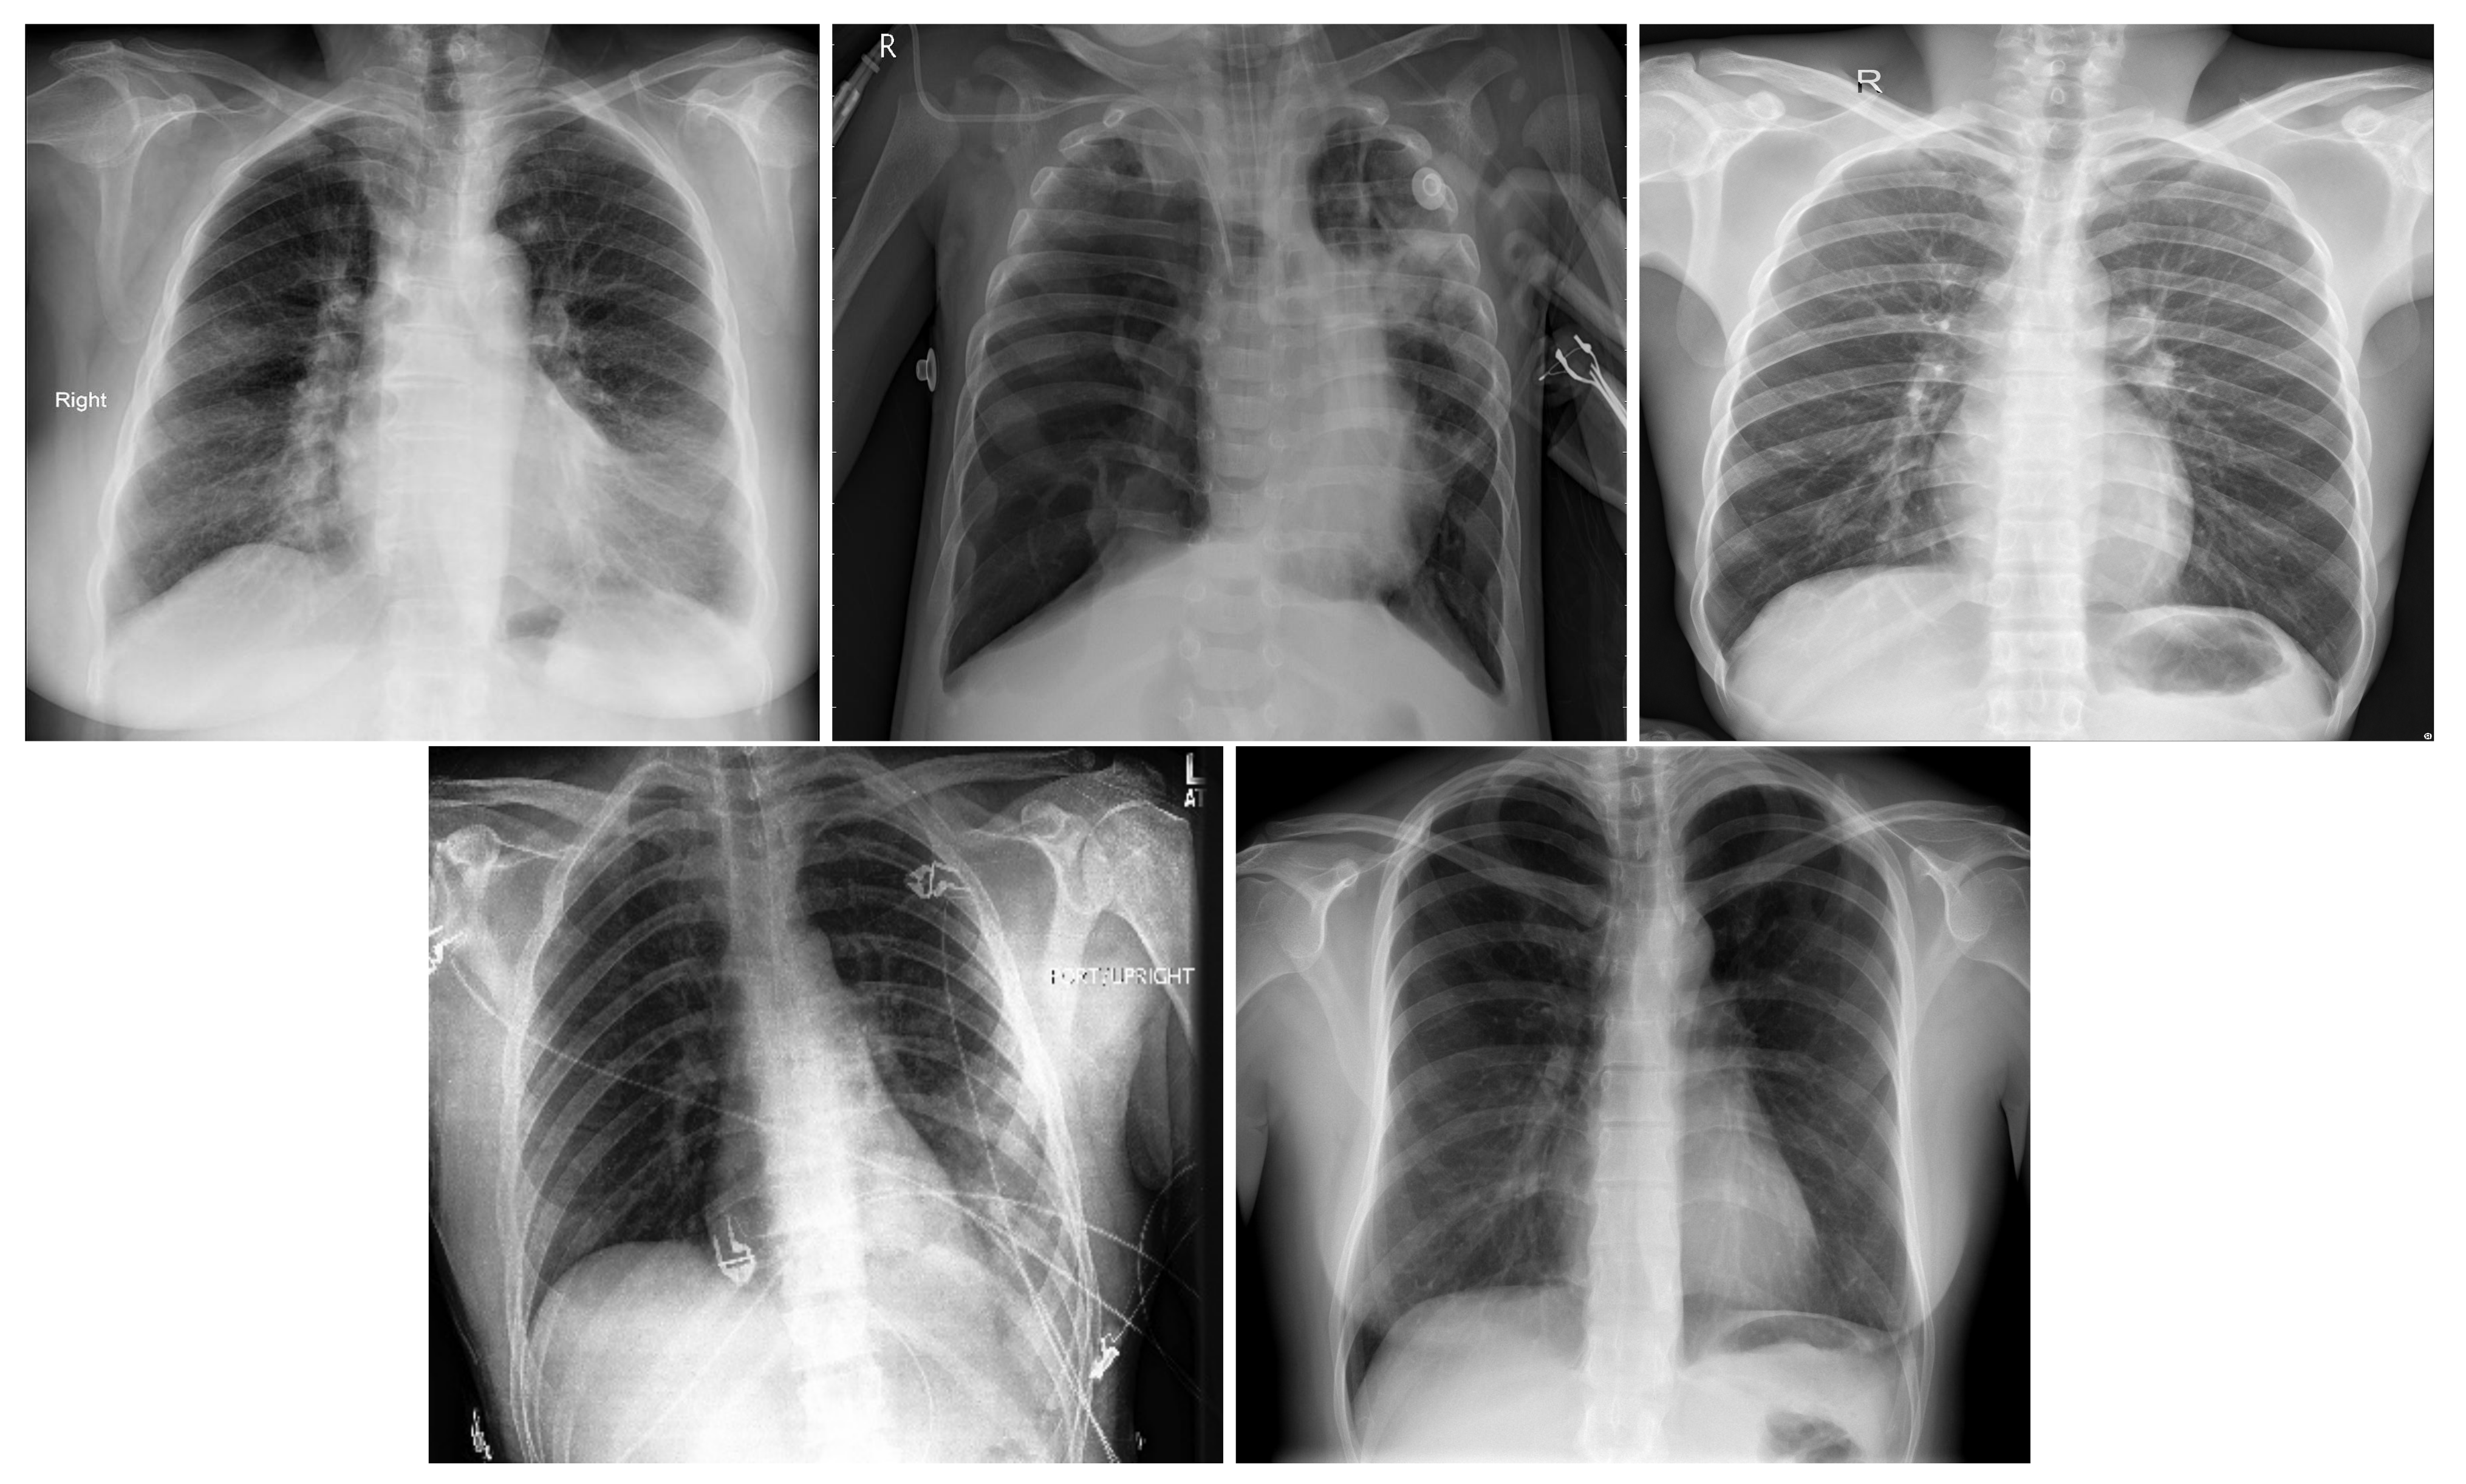

Table 2 summarizes the three-class database number of images by split and their resources. Figure 1 shows an X-ray example for each class of the three-class COVID-19 database.

In order to distinguish between COVID-19 and the other lung diseases and healthy cases, we created a five-class COVID-19 database. In fact, COVID-19 is a viral pneumonia, so we aim to distinguish between Bacterial, Viral Pneumonia, COVID-19, and Healthy cases. In addition, we considered Lung Opacity Not Pneumonia diseases as the fifth class. Similar to the three-class COVID-19 database, we used data augmentation techniques to obtain augmented data to train our models. The same data augmentation techniques were applied for the training split to obtain 12 augmented images for each image. Table 3 summarizes the five-class COVID-19 database number of images by split and their resources. Figure 2 shows an X-ray example for each class of the five-class COVID-19 database.

Figure 2. In order: COVID-19, Viral Pneumonia, Bacterial Pneumonia, Lung Opacity, Normal.